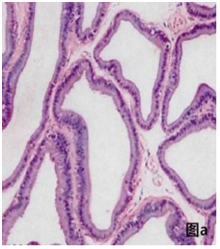

血常规和尿常规中白细胞含量增多,前列腺间质或腺腔炎细胞浸润。

部分结果展示